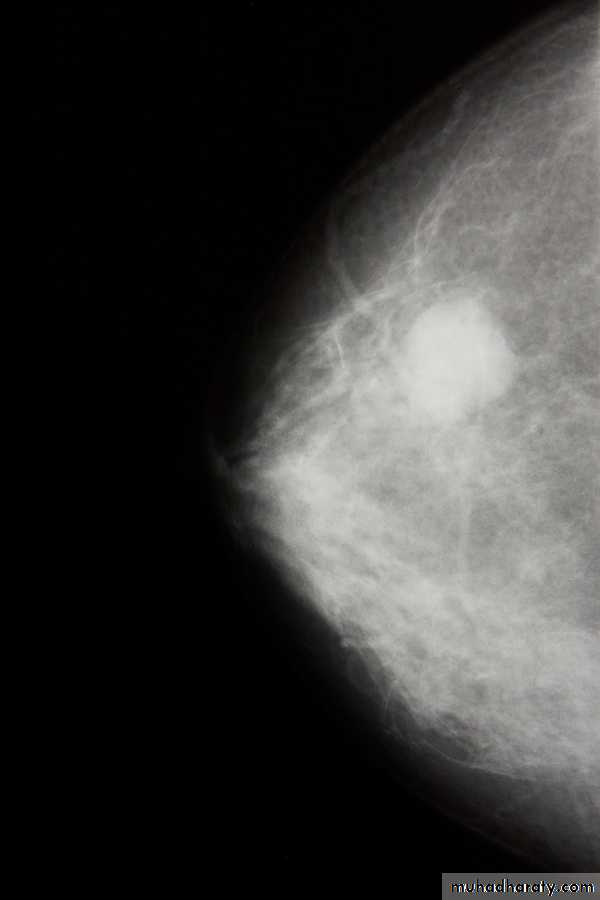

Investigations: ( 1) mammaography: soft tissue radiographs are taken by placing the breast in direct contact with ultrasensitive film and exposing it to low-voltage, high amperage x-rays. The dose of radiation is very low so it is a safe investigation. The sensitivity of this investigation increases with age as the breast becomes less dense. In total, 5% of breast cancers are missed by population –based mammographic screening programme , even in retrospect , such carcinoma are not apparent.

. Thus, a normal mammogram does not exclude the presence of carcinoma. Digital mammography is being introduced, which allow manipulation of the images and computer aided diagnosis. Tomo-mammography is also being assessed as a more sensitive diagnostic modality.